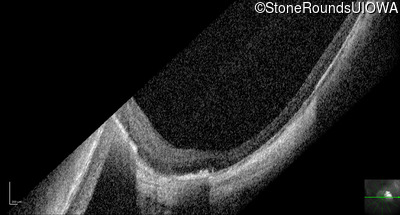

Optical Coherence Tomography - Left - 20/40

Exemplar / OCT Stack

OCT Stack